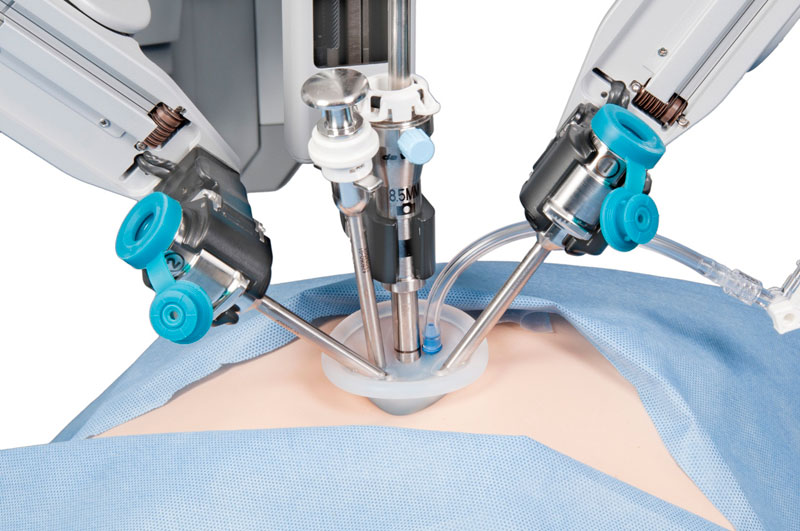

Впервые в России выполнена робот-ассистированная операция с использованием системы «Da Vinci» на грудном отделе позвоночника по поводу оссифицированной грыжи межпозвонкового диска с компрессией спинного мозга

Проведены операции с применением роботизированного хирургического комплекса «Da Vinci» при опухолях средостения — вилочковой железы

Первая робот-ассистированная тиреоидэктомия аксиллярным доступом на хирургическом комплексе Da Vinci

Первая робот-ассистированная лобэктомия

Первая робот-ассистированная экстирпация матки

Первая робот-ассистированная операция на сердце — аортокоронарное шунтирование

Первая робот-ассистированная операция аорто-бедренного шунтирования

Первая робот-ассистированная невриномэктомия из заднего средостения